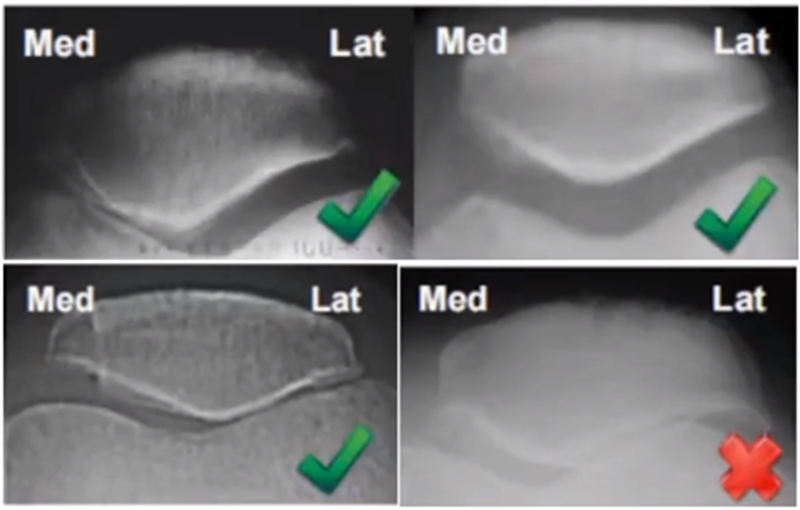

三、单髁置换的适应证——标准侧位片

标准侧位片,内外髁完全重叠,胫骨平台也一样,如果检查不标准,X线片结果会影响判断。

侧位片可以显示胫骨平台磨损部位,在判断前交叉韧带功能是否完好方面有重要意义。当磨损部位在前方或中前方,没有延伸到胫骨平台后缘时,说明前交叉韧带功能正常;当磨损部位延伸到胫骨平台后方,甚至引起后方半脱位状态时,说明前交叉韧带功能缺失或损害,此时不适合做单髁。

AMOA的侧位X线表现

ACL功能完好是单髁重要的适应证。当ACL失去功能,导致后方软骨磨损或者骨缺损,此时为整个内侧或全间室的骨关节炎,不是单髁的适应证了。

在牛津单髁标准教程里,表明前交叉韧带与后交叉韧带都应该保持功能正常,才是单髁的适应证。